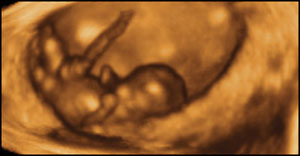

Here is a picture of her unborn baby, the picture that changed her mind:

A few days later, she showed up at the pregnancy center. She and the ultrasound tech watched as the baby seemed to wave, jump and turn. They listened to the baby’s heartbeat … and tears of joy fell from her eyes. She was so happy to have this precious child safe and secure.

She was right. Once she saw her nine week baby on the ultrasound screen, she knew that she couldn’t go through with the abortion.